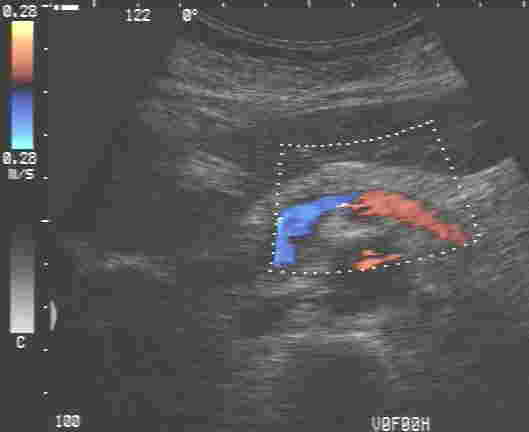

| Organe des Bauchraumes |

| Bauchgefäße | |

Dazu kommen neben dem üblichen schwarz-weiß Bild auch moderne Verfahren zum Einsatz wie Farbdopplersonographie und Kontrastmittelsonographie der Leber.